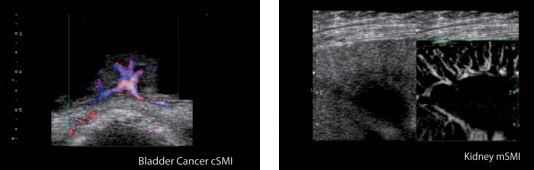

SMI具有两种成像模式:彩色(color )模式和灰阶(monochrome)模式

彩色模式(cSMI):同时显示组织的二维灰阶信息和彩色血流信息

灰阶模式(mSMI):抑制组织的二维灰阶信息,利用灰度信号来凸显血流信息